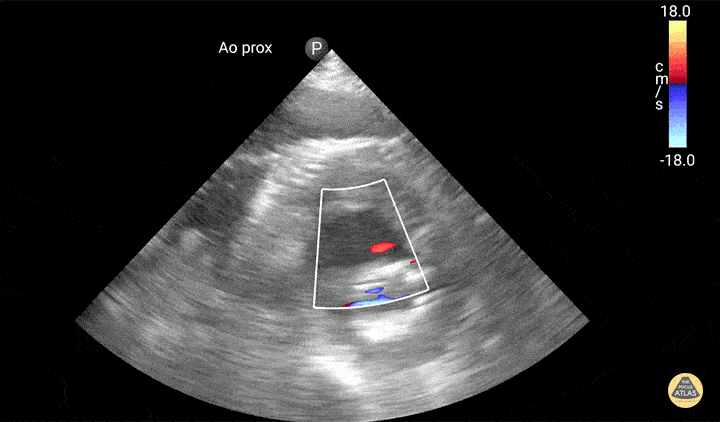

Aorta - Aortic Graft Endoleak

Active extravasation is seen through endograft into false lumen. Known chronic endoleak, but CT 30 minutes prior to this study showed no active extravasation or impending rupture. Keep an open mind when reassessing your patients, and try not to anchor too much on prior results or others' opinions! Dr. Jaffa